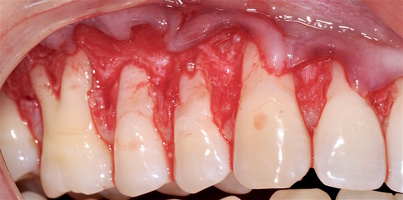

В области от 1.6 до 2.6 и от 3.6 до 4.6 все зубы имеют некариозные поражения разной степени, такие как эрозии эмали и клиновидные дефекты, вовлекающие в процесс ткани эмали и дентина. Подвижности зубов не выявлено (рис. 1а-е) [9].

При анализе и описании компьютерной конусно-лучевой томографии (рис. 2а-г) была выявлена генерализованная первичная дегисценция вестибулярной пластинки кости от 1/2 до 3/4 длины корней зубов, зубной ряд целостный, все зубы витальны, кариозных поражений нет. Тип кости 1-2 (Lechkolm и Zarb, 1983), первичная дегисценция вестибулярной костной пластинки превышает пределы возрастной атрофии.

1. ГР — глубина рецессии, (рис. 3);